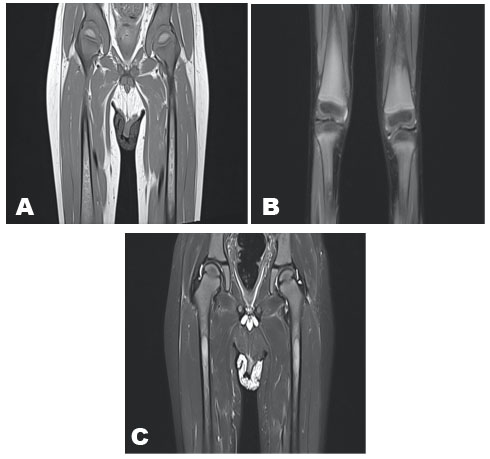

We report the case of a 5-year-old child with a known medical history of Gaucher disease type 3, who presented with deformities of the inferior limbs and complaints of bone pain. Upon evaluation, radiographic examination of the limbs revealed a characteristic triangular appearance of the metaphyses, with an indistinct boundary between the cortex and medulla, consistent with the Erlenmeyer flask deformity (Figure 1).

Additionally, during the assessment, an incidental finding of a serpiginous sclerotic area was noted in the lower left femoral metaphysis, raising suspicion of bone infraction.

Figure 1: Femurs X-ray showing the triangular contour of the metaphysis, the indistinct boundary between cortical and medullary, typical of the Erlenmeyer flask deformity in Gaucher disease. Incidentally, there is an area of serpiginous sclerosis in the lower left femoral metaphysis, suggestive of infarction.

Bone involvement is a recognized feature of Gaucher disease and can lead to significant morbidity. The Erlenmeyer flask deformity, observed in the radiographic examination, is a classic finding attributed to abnormal bone remodeling due to the infiltration of glucocerebroside-laden macrophages. This deformity often occurs in long bones and is characterized by the widening of the metaphyses with a characteristic triangular appearance [3].